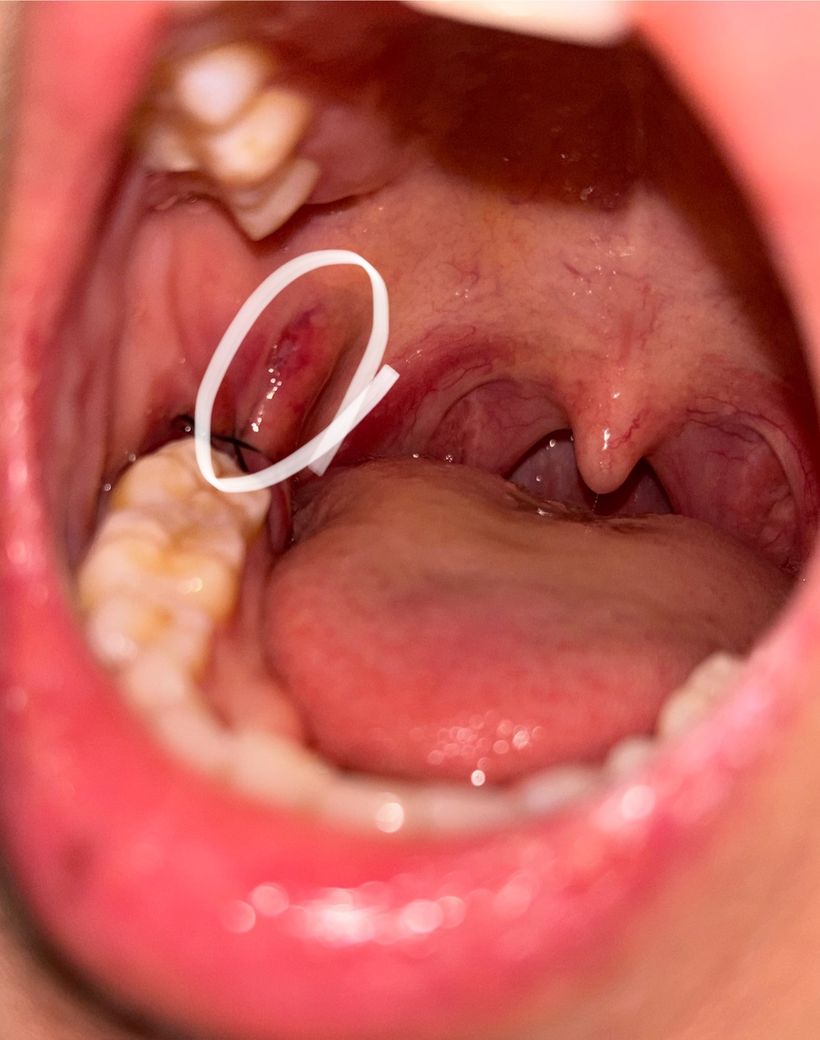

사랑니 발치 후 거울로 입안을 봤더니 사진과 같이 볼쪽까지 째서 뽑으셨더라구요. 근데 사랑니 뺀 부분만 꼬매놓으셔서 볼 쪽은 점점 더 붓고, 째진 부분이 달랑달랑 거리고 씹혀서 불편합니다. 완전 매복도 아닌데 절제 범위가 원래 이렇게 넓나요?ㅜㅜ 가만히둬야할지 약이라도 발라야할지 고민입니다..

• 1번 째 사진

사랑니 발치시 매복이 깊은경우에는 절개 범위가 생각보다 넓습니다. 저정도 잇몸절개를 하는게 맞습니다.

사랑니가 위치한 게 수직이어서 그렇지 완전매복 맞습니다. 더 원활한 발치를 위해 절개를 크게 한 것 같습니다

해당 부위 오라메디 연고 발라줘도 좋고, 일단은 발치 후 주의사항 잘 지키면서 약 복용하시면 됩니다.